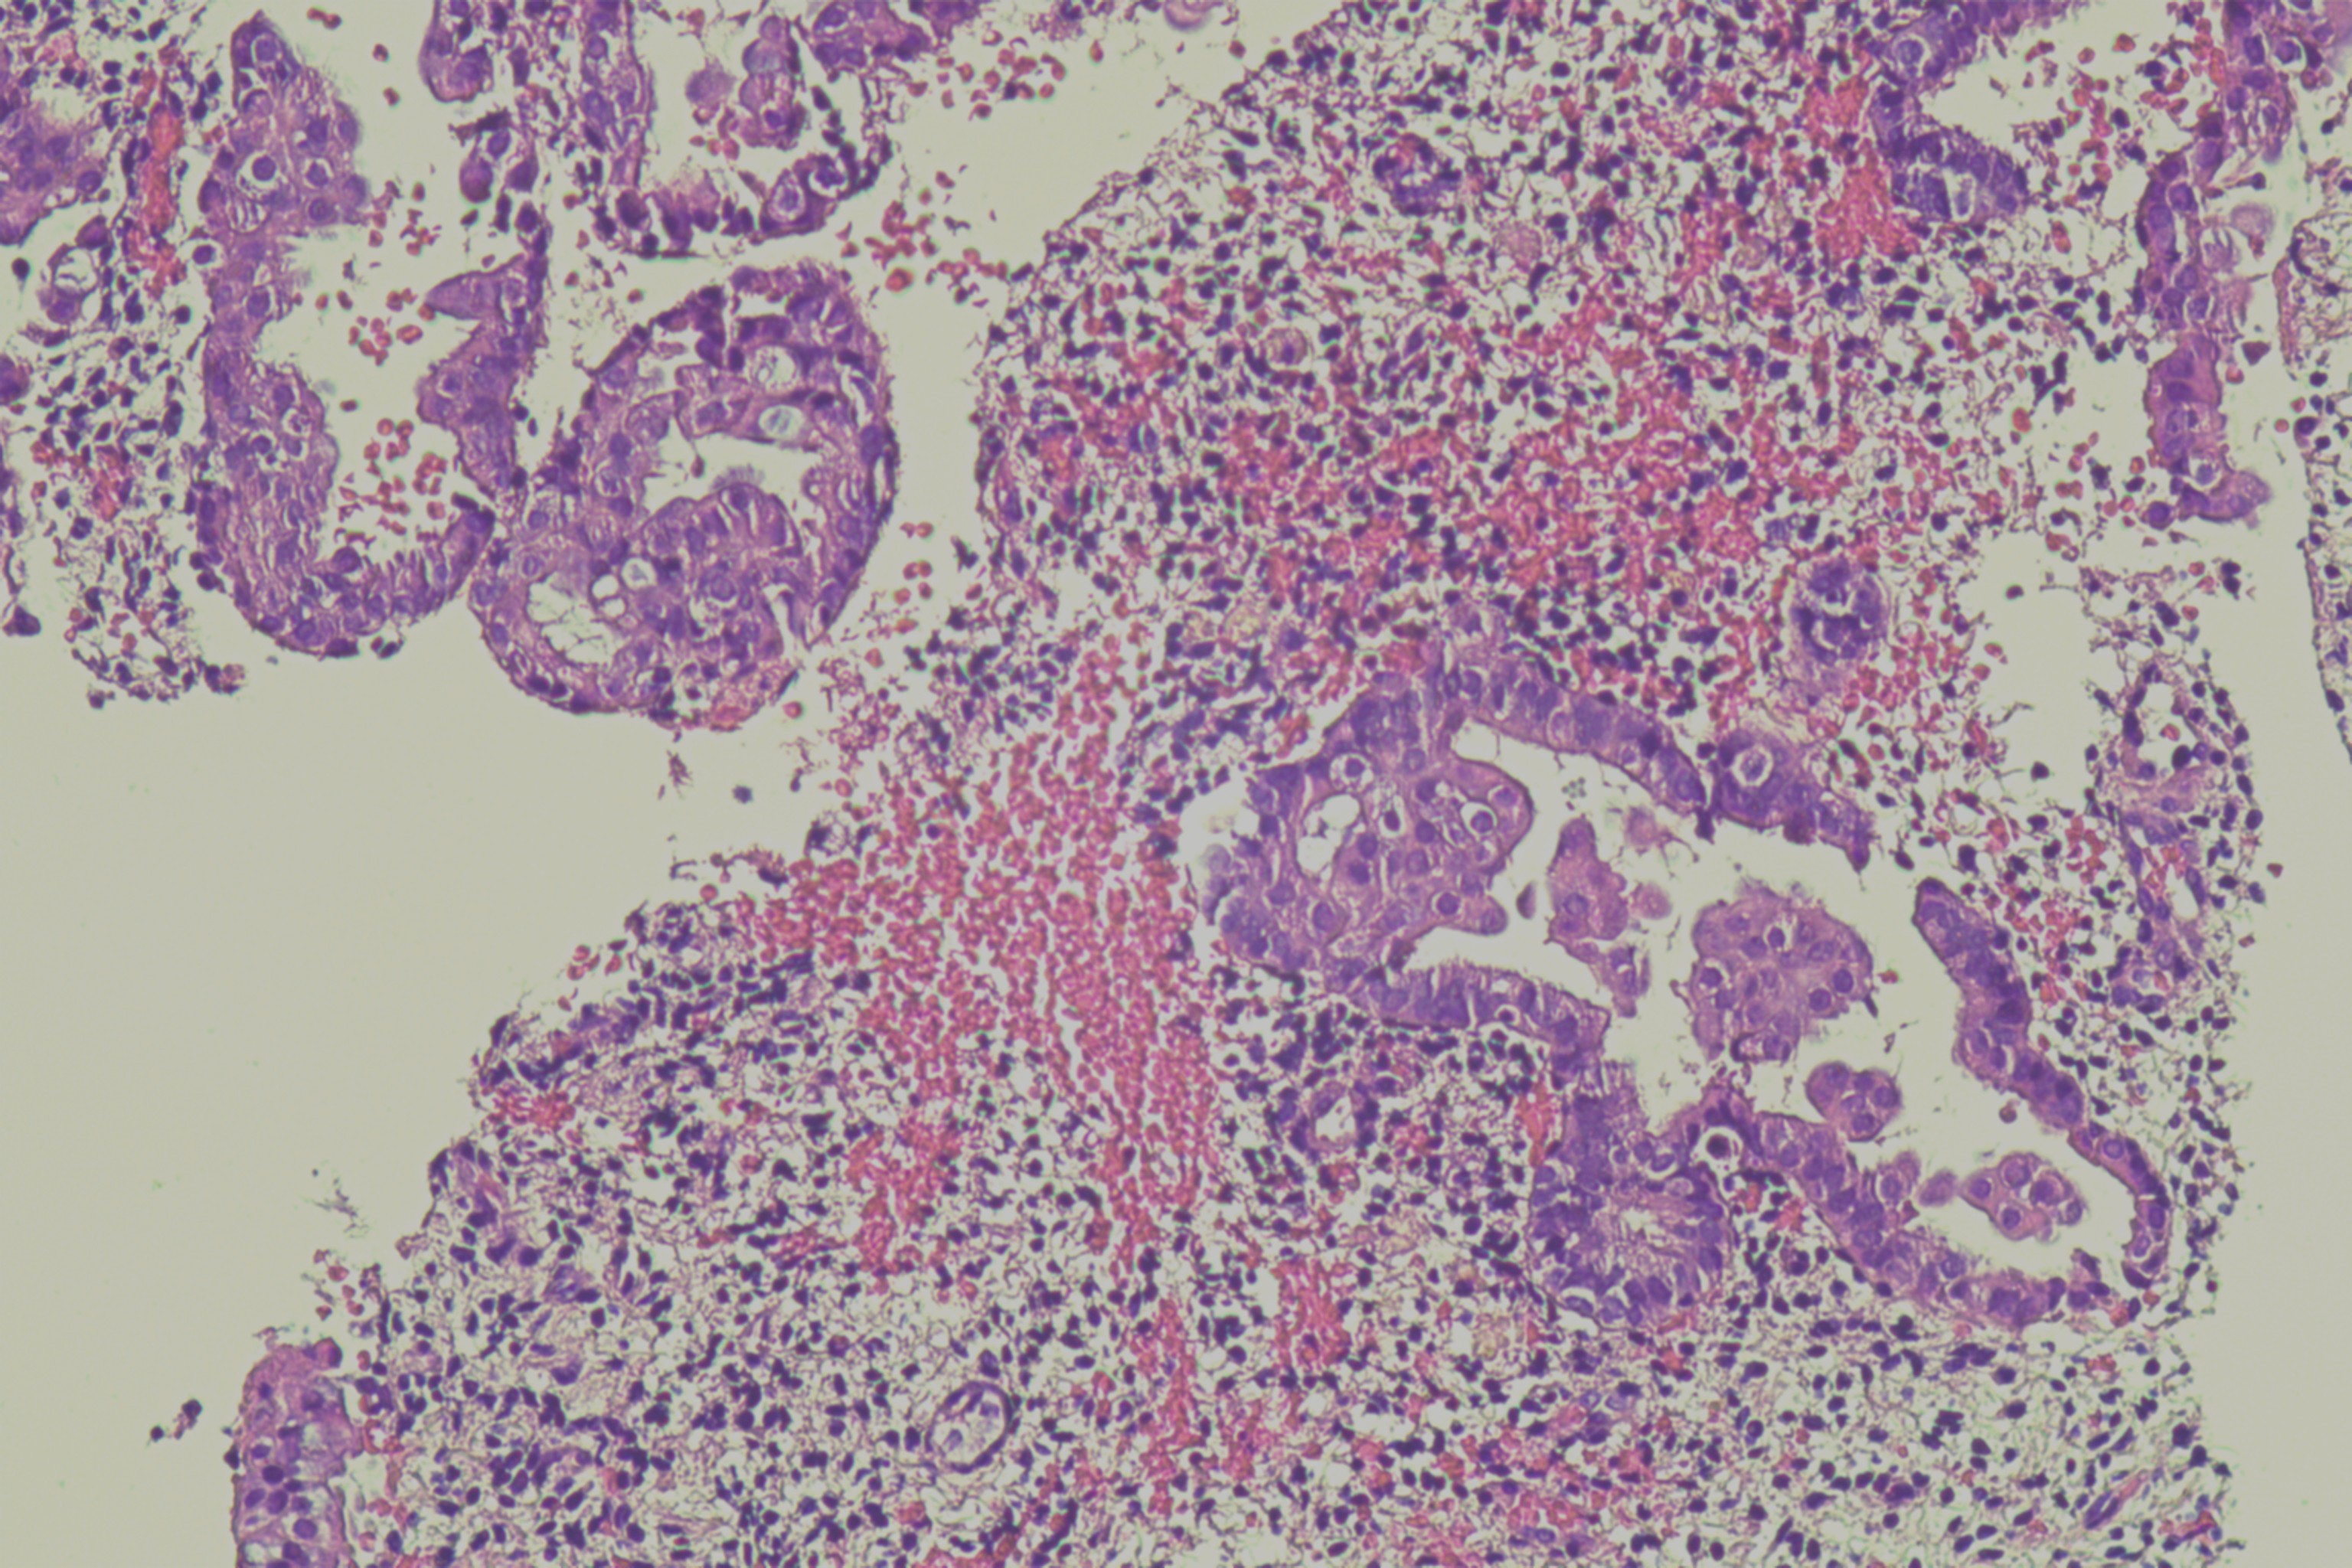

子宫内膜有无非典型性?

月经紊乱1年余,子宫增厚11月

宫腔刮出物

2.8*2.3*0.5cm灰红碎组织一堆。

嗜酸性乳头状化生。

未见非典型增生考虑为子宫内膜单纯性增生部分区域腺体呈复杂性增生(图6)伴部分腺体呈嗜酸性乳头状化生

局灶非典型性增生伴嗜酸性乳头状化生